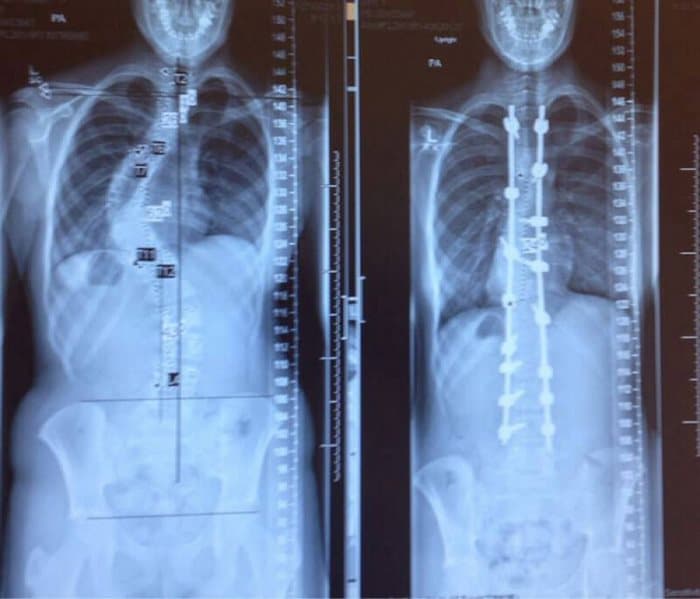

4. Μια ακτινογραφία της σπονδυλικής στήλης κάποιου πριν και μετά της θεραπείας για τη σκολίωση.